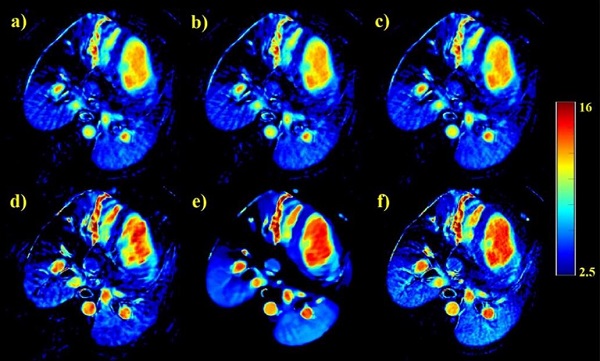

针对动态心肌灌注CT中连续扫描给患者带来的过大剂量累积问题,研究团队提出基于时变特征先验辅助的动态心肌灌注CT重建算法(TFP-SR)。该算法在数据采集过程中对基线图像和动态对比增强图像采用不同的扫描协议:对于基线图像,即在显像剂到达组织器官前,采用全采样协议进行图像采集,并通过传统FBP算法对基线图像进行重建;对于动态增强图像,采用稀疏低剂量扫描协议进行图像采集。图像重建过程中,将基线图像与动态增强图像的时变信息同时结合在CT重建数学模型中,并基于重构的数学模型进行迭代重建。提出算法在实验中取得了良好的成像效果,有望将临床动态心肌灌注CT成像的辐射剂量降低到现行剂量的5%以下(图4)。相关研究成果发表在Physics in Medicine and Biology 期刊上(Vol. 66, No. 4: 045012, 2021)。

4  动态心肌灌注CT成像结果,(a) PWLS-TV,(b) PICCS(c) PWLS-ndiSTV(d) RED-CNN(e) 提出方法,(f)HDCT